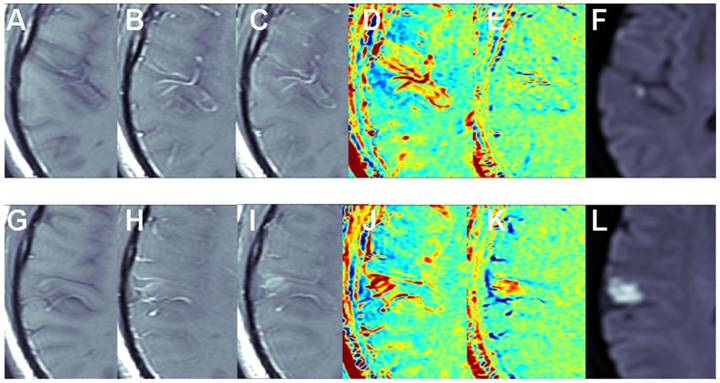

The benefit of the subtraction scheme for subtle BBB opening: Figure 2 shows two adjacent slices of a small stroke. When subtracting the image acquired pre contrast from the delayed image acquired ~15 min post contrast it is difficult to differentiate between swollen vessels and BBB opening since both result in positive signals. However, when the first image post injection is subtracted from the delayed image post contrast (acquired ~15 min later), the vessels appear blue, while BBB opening remains red, enabling clear differentiation between vessels and BBB compromise.

Figure 2

The benefit of the subtraction scheme for subtle BBB opening. T1-MRIs of two adjacent slices (A-F and G-L) of a small stroke pre-contrast (A, G), immediately post contrast (B, H), and ~15 min post contrast (C, I). Maps calculated by subtracting the pre-contrast images from the images acquired ~15 min post contrast (D, J) show both vessels and BBB disruptions as positive signals (red). Maps calculated by subtracting the immediate post-contrast images from those acquired ~15 min later (E, K) show vessels as negative signals (blue) and BBB opening as positive signals (red).